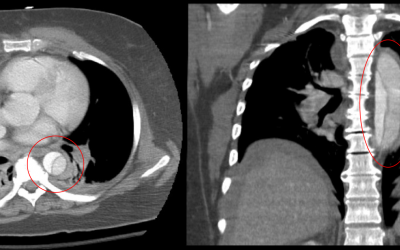

Point-of-care ultrasound (POCUS) is often taught to answer binary questions, like, "Is there free fluid in the abdomen?" However, when we combine POCUS images with clinical documentation, we are telling a story — and every good story has a beginning, middle, and end....